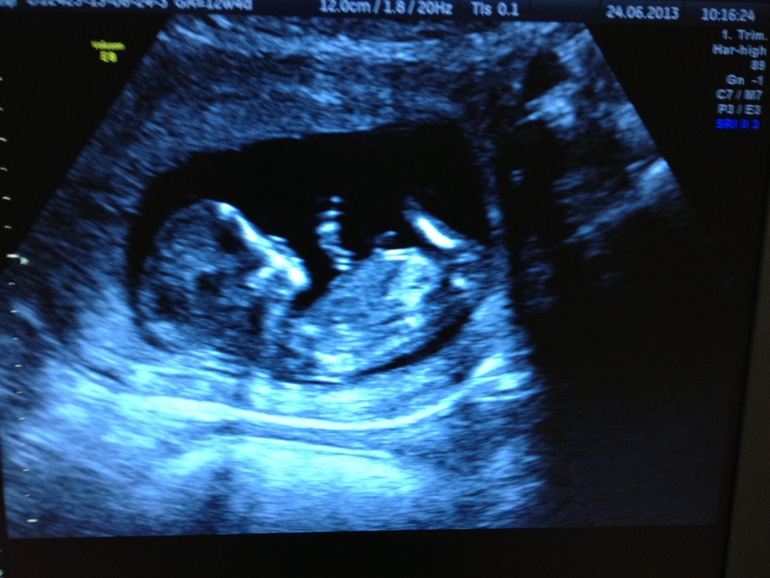

Ну вот и я прошла 1 скрининг)))

УЗИ, КТГ, доплерсказали что все хорошо, КТР 61,4, соответствует сроку 12 нед и 4 дня! Сердцебиение 155 уд/мин! Вообщем все визуализируется, все хорошо! Сфоткала свою лялю на телефон! Показала мужу-сказал девка, яички типа не опущены как это у мальчиков опускаются, говорит вроде высоко они! А я смотрю и мне кажется низко, почему то появилось ощущение что там мальчик опять! Как то еще по сердцебиению тут многие определяют что иногда сходилось, так вот наше сердцебиение 155 уд/мин больше похоже на мальчика или девочку, кто знает? И как вам кажется кто на фото? Ну просто для интереса)))Может есть тут узисты))))

)))))))))))))где он там вообще мог рассмотреть отсутствие или наличие яичков

вы врач??? Он предположил что под ногой это яички светятся! С первым ребенком вообще он определил пол и показал узистке, хотя он не узист, а стоматолог! Сказал что вероятнее всего это яички!

Zhenya

да он не утверждал! Просто когда я ему показала только фото - первое у него впечатление сложилось что они высоко! Сейчас уже тоже говорит не знаю, не понятно! Конечно по фото тяжело вообще что-либо понять!

Вот и я о том же, именно про фото, что на нём все одинаковые) У меня фотка на 12 неделе, мне кажется- вылитая девочка, некоторые вообще не поймут, где голова, где ноги

да не за что. Яички еще не опустились в мошенку в таком сроке. И половые органы одинаковые. Но врачи некоторые определяют по уровню наклона пиписки)))) ну у вас малыш расставил ножки и вроде по наклону девчуля. Потом отпишитесь;)

да? А я читала что вроде как опуститься должны уже, а муж тоже сказал что наверно еще не опускались! Вы даже по наклону как то умудрились рассмотреть)))) Я там кроме одной ноги ничего не вижу